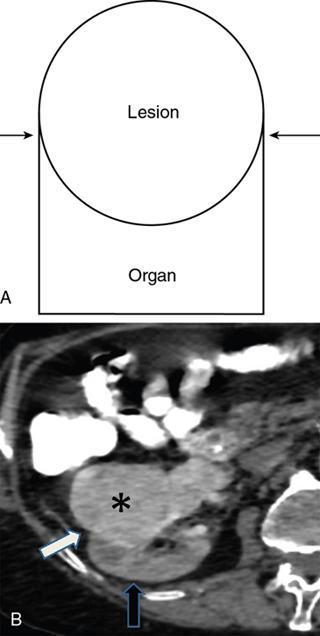

• Beak sign

• If a mass deforms the margin of an adjacent organ into a beak shape, then the mass probably originates from that organ – this is the positive ‘beak sign’. On the contrary, if the mass has dull edges or fuzzy margins (no sharp beak seen) with adjacent organs, it indicates that the mass probably does not arise from the organ but just compresses it (Figs. 10.17.2.210.17.2.3).

Fig. 10.17.2.1 Positive beak sign – Drawing (A) shows beak-shaped interface (arrows) of lesion with organ. Axial CT (B) shows sharp beak like interface (white arrow) between the retroperitoneal enhancing mass (asterisk) and the kidney (black arrow) which implies the lesion arises from the organ.